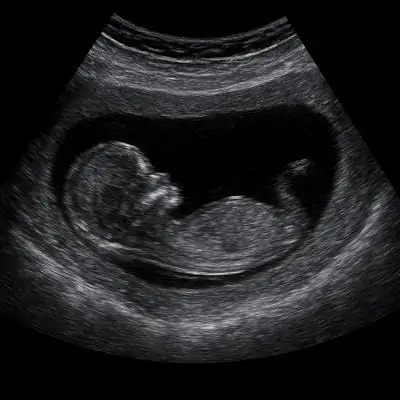

Vaginal Ultrasound Dubai is a safe and non-invasive procedure designed to assess your pelvic and reproductive health. By placing a small probe inside the vagina, detailed images of the uterus, ovaries, and surrounding pelvic organs are captured. Each session is personalized according to your needs—whether it is a routine health check, fertility tracking, or investigating abnormal bleeding.

The procedure works by inserting a small probe into the vagina, which emits high-frequency sound waves. These waves create precise images of the uterus, ovaries, and nearby organs. The images help your gynecologist or radiologist to detect abnormalities, monitor early pregnancy, and evaluate overall reproductive health.

• Monitors early pregnancy and fetal development.

Yes! Vaginal ultrasound is completely safe and often recommended for early pregnancy to ensure precise monitoring of fetal development.